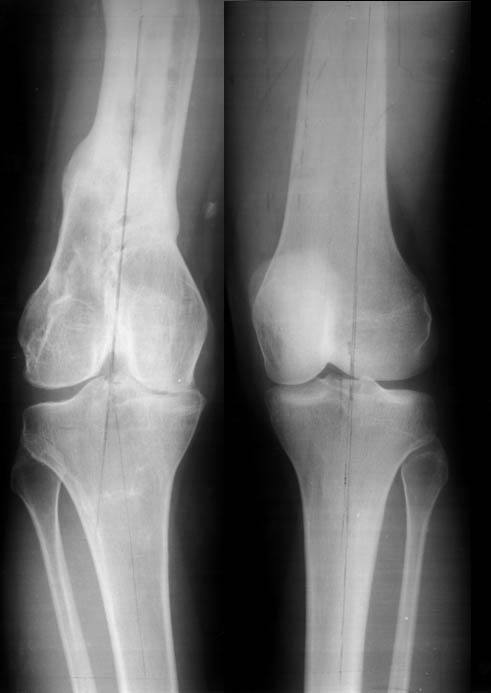

Переломы конечностей лечились АВФ.В настоящее время стойкая разгибательная контрактура правого коленного сустава (сгибание 105-110 гр., разгибание 160-165 гр.), варусная деформация, болевой синдром.

Даже по этим коротким снимкам видно, что варусная деформация на уровне бедра. Хотя для полноценной оценки оси сделать надо снимок всей конечности, от таза до стопы. Наклеить метки на кожу, по которым сделать склейку. И профиль бы тоже неплохо посмотреть.

Уважаемый Антон, при определении уровня остеотомии и величины коррекции руководствуемся, обычно, необходимостью обеспечить нормаль механической оси к середине опорной поверхности большеберцовой кости. Расчет производится по рентгенограмме (рентгенограммам) конечности под нагрузкой, которые визуализируют положение головки бедренной кости относительно таранной кости. На представленных рентгенограммах определить эти реперные точки (и заслужить Вашу зараннюю благодарность) не представляется возможным. Остается неясным с каким исходом сросся перелом правой большеберцовой кости. Складывается впечатление, что нанесены не механические, а анатомические оси. Исправлять проще за счет "минус - кость", но механически правильнее "плюс". Чтобы выполнить механические требования, иногда на ряду с угловой коррекцией (деваризация-экстензия, т.к. имеется не только разгибательная, но и сгибательная контрактура)необходимо медиолатеральное смещение.

Согласно тому же Палею следует выделять 4 причины деформации (вальгусной или варусной) в области коленного сустава. Это требует выполнения доплнительных снимков (с распоркой в области колена и пр...).

Уважаемый Антон, видимо перелом большеберцовой кости на механическую ось не повлиял, но явно варусная деформация усугубляется повреждением наружного связочного аппарата (МКС.... Просится поднагрузочный R-снимок конечности и корригировать, на мой взгляд, надо бедро (+ остеотомия, если планируется мобилизация коленного сустава).